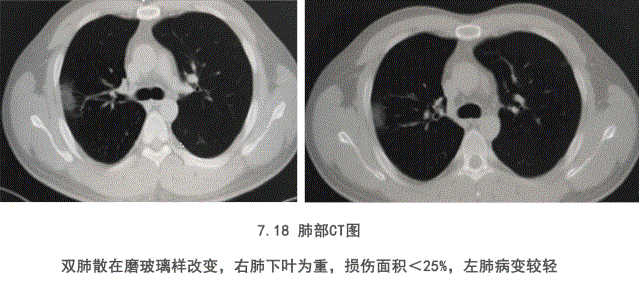

35歲的王先生(化名),是國內某知名企業(yè)的駐外員工,此次公派到非洲肯尼亞負責解決當地技術(shù)問(wèn)題。但沒(méi)想到卻中招新冠病毒,感染入院。在病情惡化無(wú)計可施的情況下,中方醫生提出給予特異性免疫球蛋白進(jìn)行治療的建議。在經(jīng)過(guò)3天的治療后,患者各項臨床指標都呈好轉趨勢,最終王先生康復出院。主治醫生也在對新冠特異免疫球蛋白治療新冠肺炎進(jìn)行總結時(shí)表示,新冠特異性免球蛋白對重癥新冠肺炎治療有效??刂蒲装Y,迅速改善癥狀,恢復體力效果顯著(zhù)。